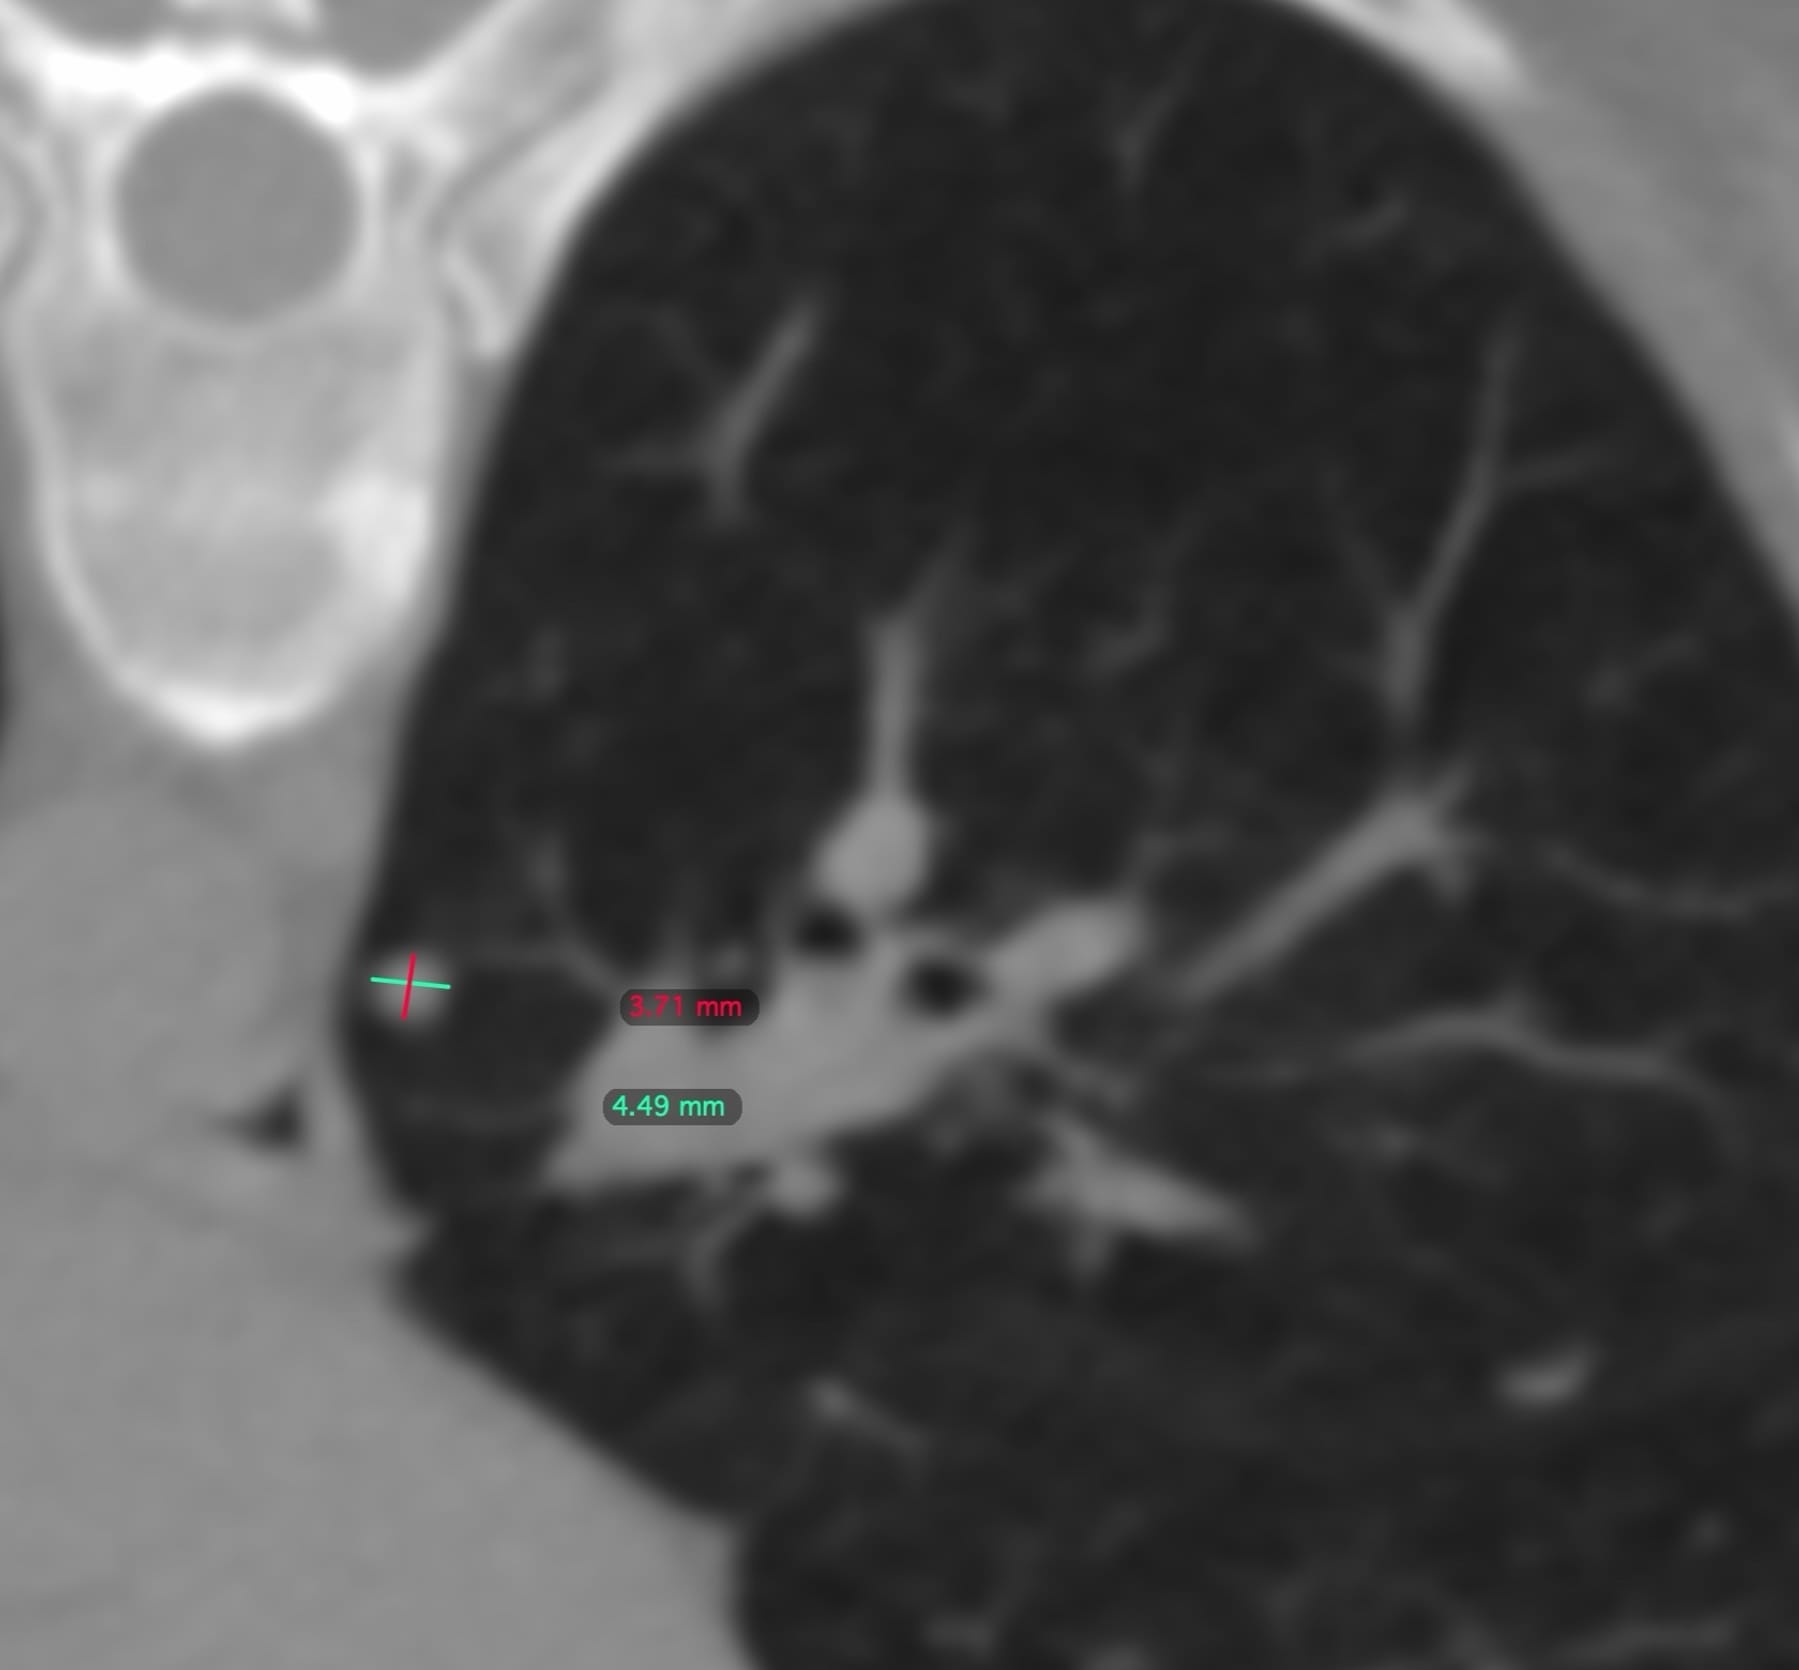

A 55-years old, recently diagnosed to have carcinoma breast, was found to have multiple < 5 mm sized lung nodules on a staging PET/CT.

She was referred for a CT guided biopsy. The left lower lobe nodule seemed to be the simplest to approach in the prone position.

The video discusses the case, the approach to this nodule, other similar nodules and basic principles of performing biopsies in sub 5 mm lung nodules.